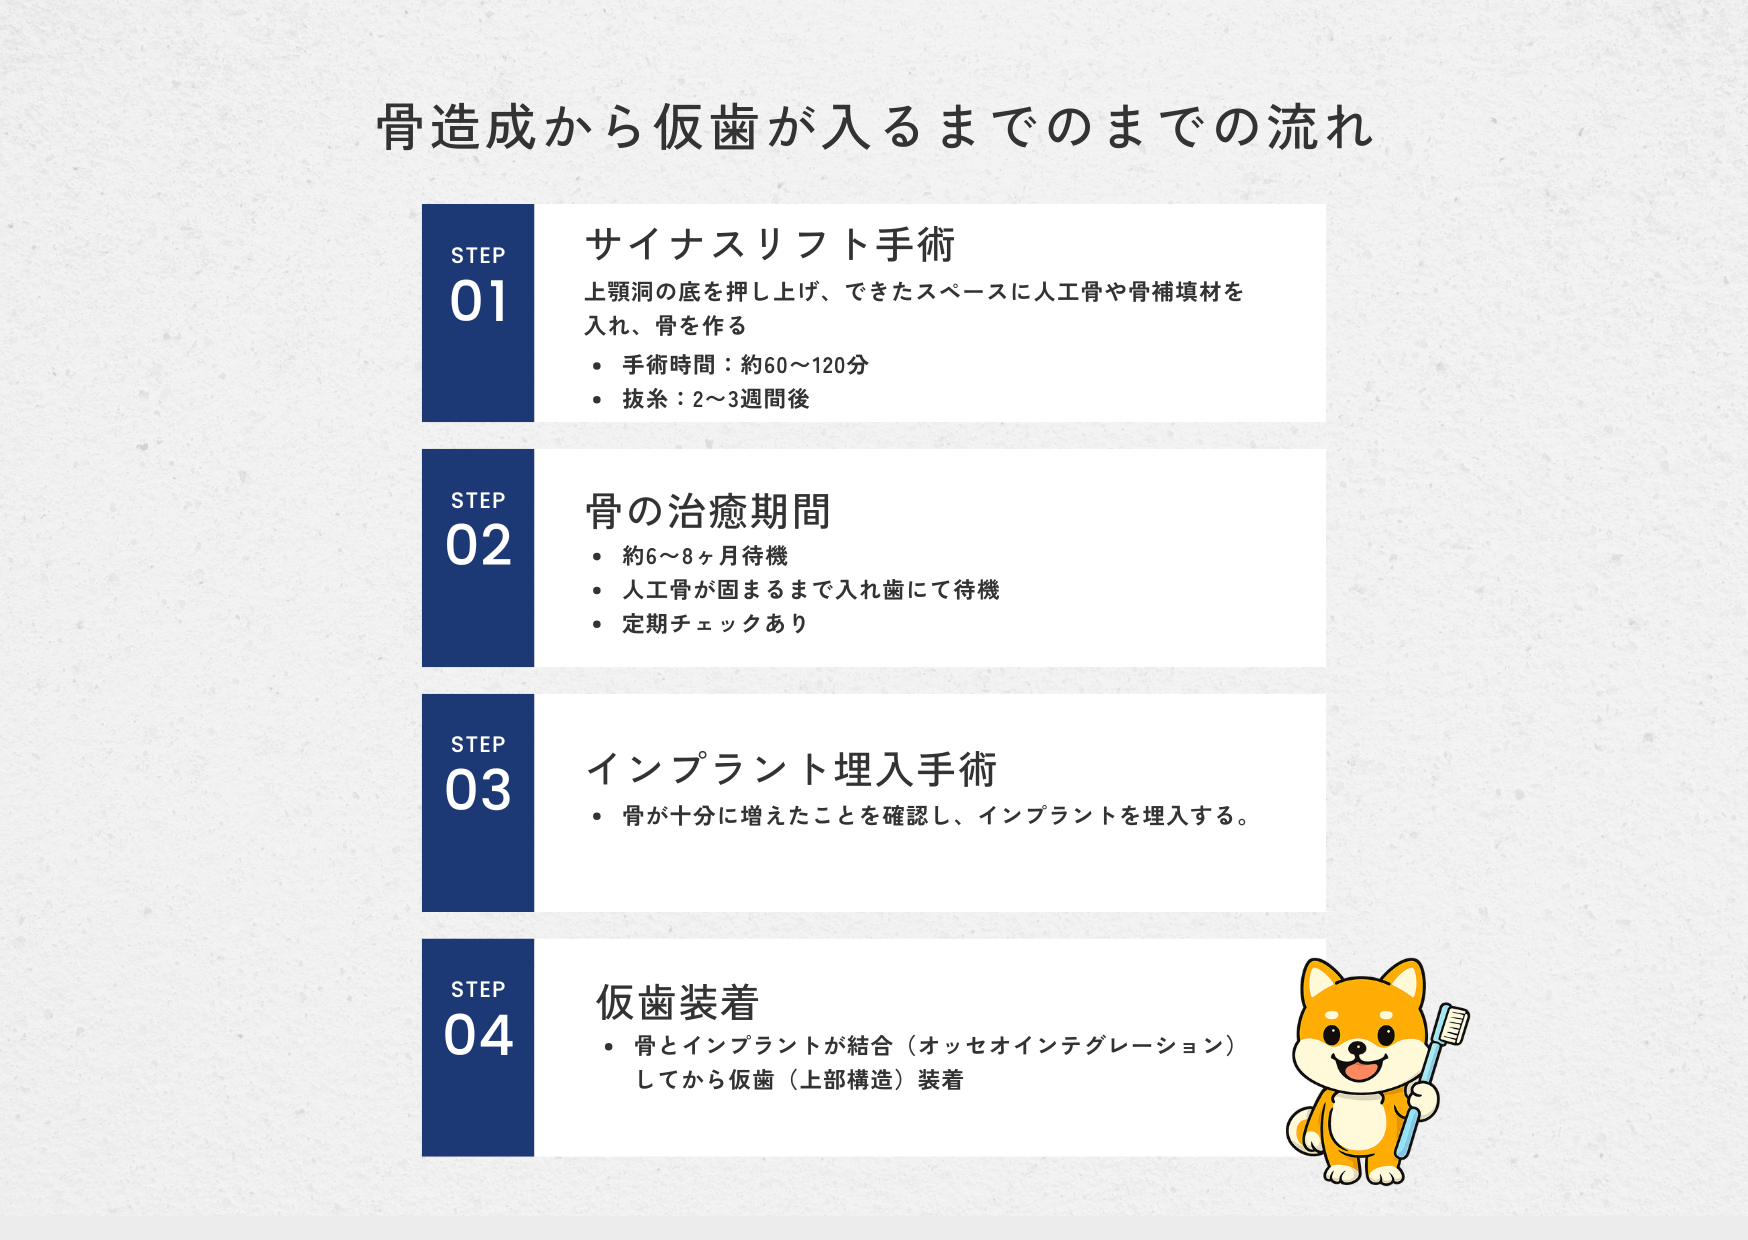

3-4. サイナスリフトとオールオン4は「同時に行わない」ことがある理由

※骨の無くなり方によってサイナスして同時埋入できる可能性もあります。

※インプラントを埋入後、インプラントと骨が結合するまで入れ歯にて待機することがあります。

CTで精密検査を行った結果、上顎の骨の厚みが不足している状態でした。そこでまず行ったのがサイナスリフトです。

①サイナスリフトを実施

上顎洞の粘膜を持ち上げ、骨補填材を填入

②サイナスして骨ができるまで待機

骨は一瞬でできるもではありません。しっかりと安心した骨になるまで待つことが重要になります。

この患者さんはサイナスリフト手術後、約6ヶ月の待機期間を設けました。

この待機期間は「何もしていない時間」ではありません。骨がしっかり成熟することで、将来のインプラントの長期安定に繋がります。

③6ヶ月後に埋入オペ

CTで骨造成が十分確認できた段階で、インプラント埋入オペを実施しました。

サイナスリフトでしっかり骨ができていたため、安定した初期固定が得られ 予定通り埋入を完了することができました。

当院では、サイナスリフトによって十分な骨を造成したあと、骨がしっかり成熟した段階でインプラントを埋入するという2段階の治療を行います。